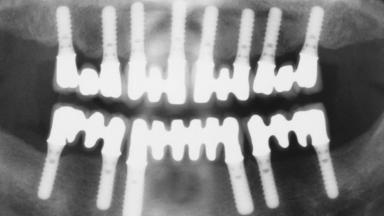

Immediate Loading of Eight Implants in the Maxilla and Six Implants in the Mandible and Final Restoration with Three-Unit and Four-Unit FDPs

German Gallucci, Jean-Pierre H Bernard, Urs C Belser

# of Implants 14

Type of Implants One-Piece

Defining Characteristics Fully edentulous upper jaw to be rehabilitated with four or more implants

Modality 6+ implants with immediate loading